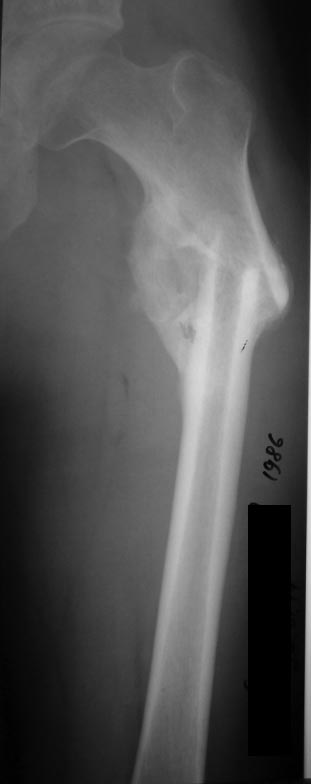

[Ortho] Предел одномоментного удлинения диафиза бедра?

Уважаемые коллеги! Предоставляем один свежих случаев, если что то не так

просим строго не судить!

С уважением Ерсин Жунусов